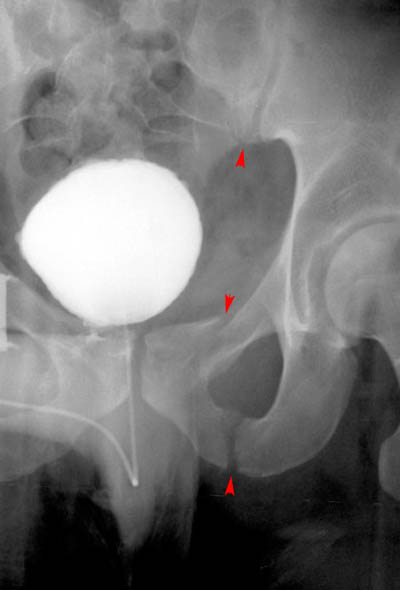

23) What abnormalities of the pelvis can be observed in the image below?

In the above image the sacroiliac joint and the ipsilateral ischiopubic rami are fractured, making the answer to the question "All of the Above."

24) Based on your findings, name the condition shown in the image above. Malgaigne Fracture